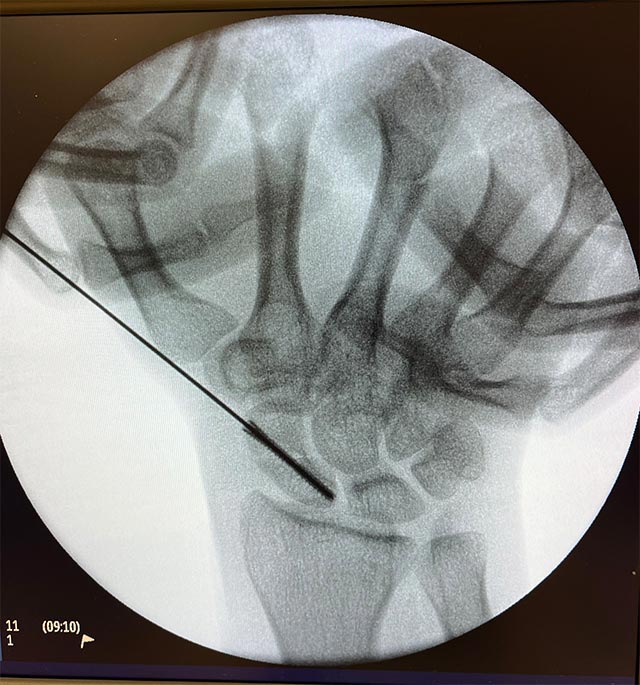

微創手術以螺絲將舟骨骨折固定

較理想的處理方法是以微創手術以螺絲將舟骨骨折的位置固定,不需額外打石膏,而螺絲亦不用再取出,術後只需要暫停6星期的劇烈運動,日常生活不受影響。